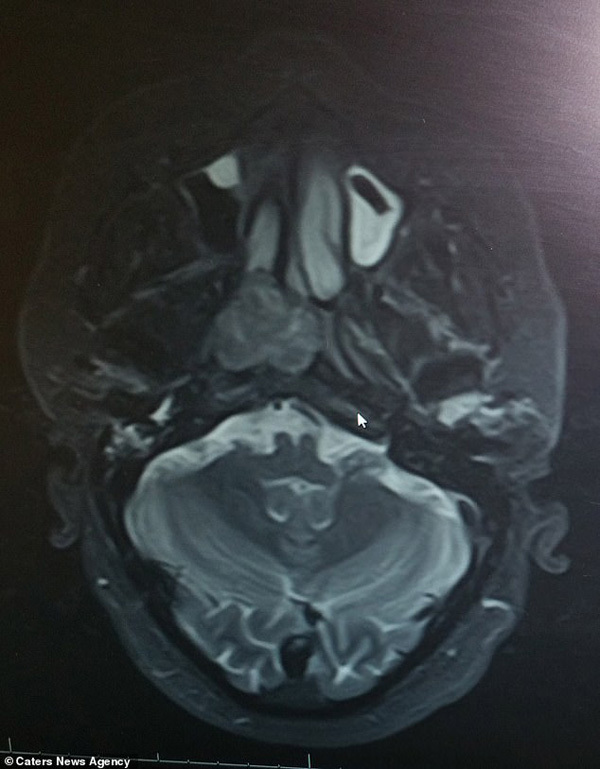

2 năm trôi qua, căn bệnh cảm lạnh mà Ben mắc phải chẳng những không thuyên giảm mà ngày càng nghiêm trọng, kèm theo đó là triệu chứng đau đầu dữ dội, ông quyết định thử đi khám một lần. Tuy nhiên kết quả lại trái với tưởng tượng, Ben không hề bị cảm lạnh, qua kết quả chụp MRI, ông được chẩn đoán ung thư biểu mô tuyến và có một khối u với đường kính 4cm nằm phía sau mũi ở đáy hộp sọ.

Ngay lập tức, ông Wilkinson được chỉ định phẫu thuật để cắt bỏ khối u. Nhưng do khối u khá to, lại nằm gần các dây thần kinh quan trọng, các bác sĩ chỉ có thể cắt bỏ một nửa để tránh ảnh hưởng đến các bộ phận khác.

Khối u phía sau mũi ở đáy hộp sọ của ông Wilkinson chỉ được cắt bỏ 1 nửa, giúp tăng thính giác của ông lên 85%, nhưng vẫn còn một nửa khối u ở lại.